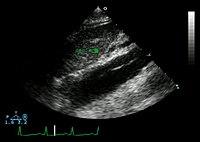

Ultrasound

An echocardiogram displaying the true lumen and false lumen of an aortic dissection: In the image to the left, the intimal flap can be seen separating the two lumens. In the image to the right, color flow during ventricular systole suggests that the upper lumen is the true lumen.

The transesophageal echocardiogram (TEE) is a good test in the diagnosis of aortic dissection, with a sensitivity up to 98% and a specificity up to 97%. It has become the preferred imaging modality for suspected aortic dissection. It is a relatively noninvasive test, requiring the individual to swallow the echocardiography probe. It is especially good in the evaluation of AI in the setting of ascending aortic dissection, and to determine whether the ostia (origins) of the coronary arteries are involved. While many institutions give sedation during transesophageal echocardiography for added patient comfort, it can be performed in cooperative individuals without the use of sedation. Disadvantages of TEE include the inability to visualize the distal ascending aorta (the beginning of the aortic arch), and the descending abdominal aorta that lies below the stomach. A TEE may be technically difficult to perform in individuals with esophageal strictures or varices.